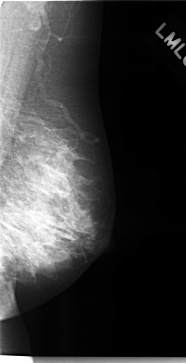

C_0127_1.LEFT_MLO

LEFT_MLO LINES 4712 PIXELS_PER_LINE 2416 BITS_PER_PIXEL 12 RESOLUTION 50 NON_OVERLAY